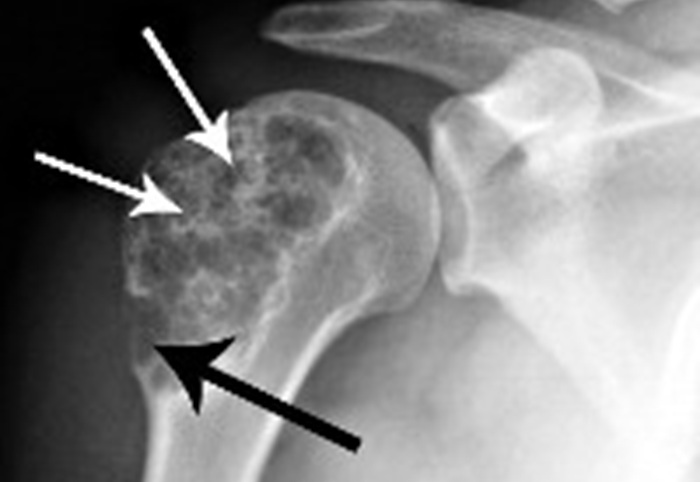

- Новообразования (доброкачественные, злокачественные).

При расшифровке снимка врач смотрит на потемнения, тени, структуру кости и на основании исследования пишет заключение.

В норме должны четко просматриваться контуры плечевой кости (без разрывов). Не должно быть затемнений, новообразований, отростков.